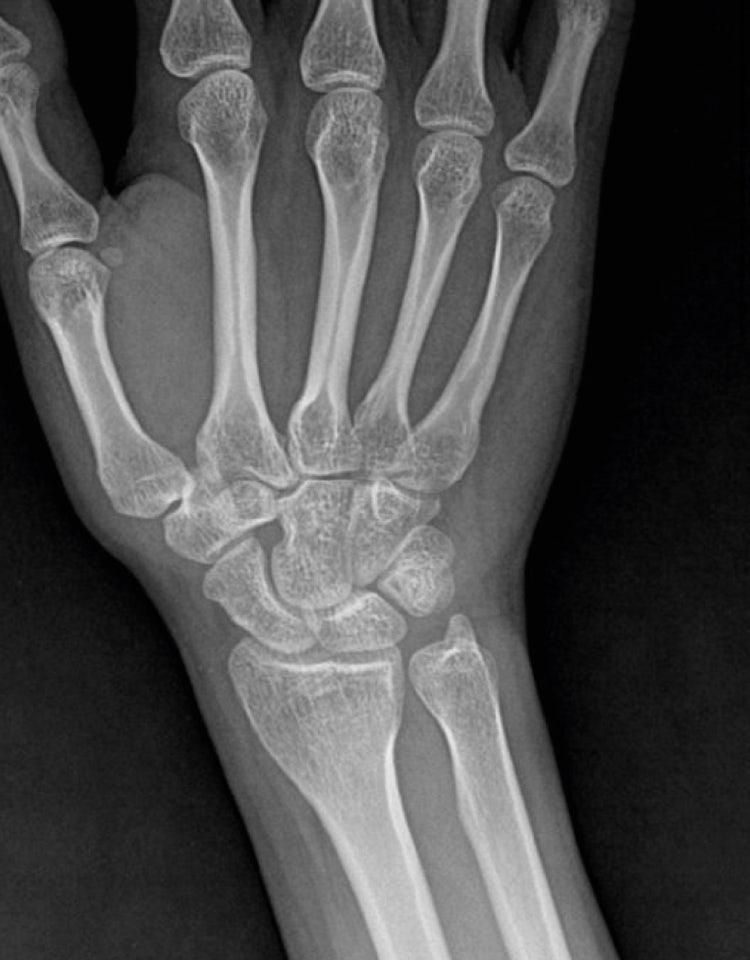

엑스레이는 예전에 손목 다쳤을때 찍어둔 겁니다만 아주 어렸을적부터 주먹을 쥐면 저렇게 검지랑 소지가 안 구부려지는데 뭔가 문제가 있는건가요?ㅜㅜ

검지와 소지가 주먹 쥘때 끝까지 안구부러진다면 선천성 힘줄 이상, 건유착, 혹은 근육 기능 저하일 수 있습니다.

어렸을 때부터 그랬다면 선천적 구조 문제 가능성이 높고 기능적 불편이 있다면 치료를 고려할 수 있습니다.